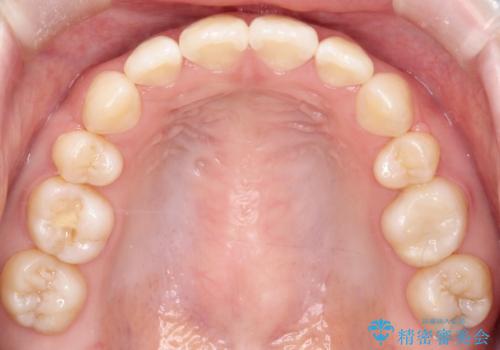

- 20代女性

- 矯正装置

- 審美装置

- ”口元を下げたい”が主訴で来院されました。

抜歯してワイヤー矯正を行い、口元も改善され大変満足していただきました。

小臼歯の抜歯を行うことで口元を改善することができました。